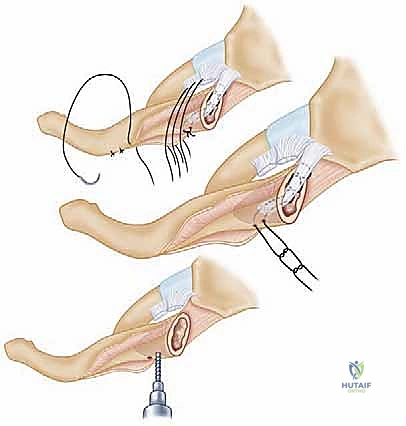

2. الشق الجراحي والوصول للمفصل

يُجري الدكتور هطيف شقاً جراحياً تجميلياً دقيقاً فوق المفصل، مع الحفاظ التام على الأعصاب الحسية والأوعية الدموية السطحية باستخدام تقنيات الجراحة الميكروسكوبية.

3. تنظيف المفصل وتقييم الغضروف

بمجرد فتح المفصل، يتم إزالة الأنسجة الندبية وبقايا الأربطة الممزقة. يتم تقييم القرص الغضروفي؛ إذا كان ممزقاً بشدة يتم استئصاله جزئياً، وإذا كان سليماً يتم الحفاظ عليه.

4. تقنية إعادة البناء (Reconstruction Technique)

لا يمكن ببساطة خياطة الأربطة الممزقة لضمان الاستقرار. لذلك، يستخدم الدكتور هطيف تقنية متقدمة لإعادة البناء باستخدام "رقعة وترية" (Tendon Graft).

* أخذ الرقعة: غالباً ما تؤخذ من وتر العضلة الرشيقة (Gracilis) أو العضلة نصف الوترية (Semitendinosus) من ركبة المريض نفسه (Autograft)، أو استخدام رقعة صناعية طبية عالية الجودة.

* حفر الأنفاق العظمية: يتم حفر ثقوب دقيقة جداً في عظم الترقوة وعظم القص باستخدام أدوات جراحية متطورة.

5. تمرير الرقعة وتثبيتها (تقنية الرقم 8)

يتم تمرير الرقعة الوترية عبر الثقوب العظمية بنمط يشبه الرقم 8 (Figure-of-eight). هذه التقنية الميكانيكية الحيوية توفر قوة استقرار هائلة تحاكي قوة الأربطة الطبيعية (الرباط الكبسولي والرباط الضلعي الترقوي).

تحذير طبي هام: في الماضي، كان بعض الجراحين يستخدمون أسياخ معدنية (K-wires) لتثبيت المفصل. الأستاذ الدكتور محمد هطيف يمنع تماماً استخدام هذه الأسياخ في هذا المفصل، حيث أثبتت الدراسات الطبية أن هذه الأسياخ قد تهاجر وتخترق القلب أو الرئتين مسببة الوفاة. بدلاً من ذلك، يعتمد الدكتور هطيف على خيوط جراحية فائقة القوة (Suture anchors) والرقع الوترية الطبيعية التي تندمج مع الجسم.